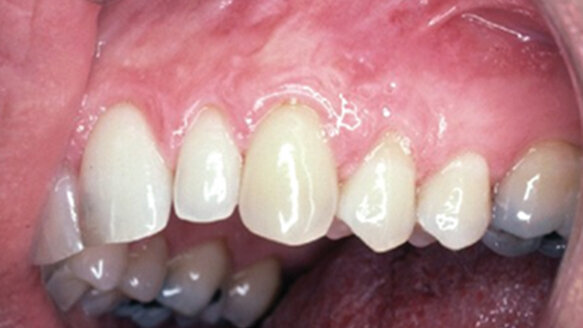

The upper left first bicuspid (#12) also had recession and root exposure, although it was not noticeable to the patient. Both the #11 and #12 were asymptomatic, but only the more noticeable #11 bothered the patient visually (see Fig. 1: Recession of the upper left cuspid #11 is of primary concern to the patient. Also present is the recession of the #12, which is of no esthetic concern to the patient. After discussion about treatment options, the patient opts not to use a membrane barrier in the treatment of the #12.).

Figure 6 shows how the color of the newly attached keratinized gingiva achieved on the previous recessed root of #11 blends in with the symmetrical background tissue, giving the esthetic appearance desired while restoring health. Note also that #12, without using the barrier GTR, does not regenerate gingival coverage and returns to the original recession level. (See Fig. 6: Gingival coverage is achieved on the previous recessed root of #11. The color of the newly attached keratinized gingiva blends in with the symmetrical background tissue, giving the esthetic appearance desired — while restoring health. Note also that #12 without using the barrier GTR does not predictably regenerate gingival coverage and results in a recession once again.)